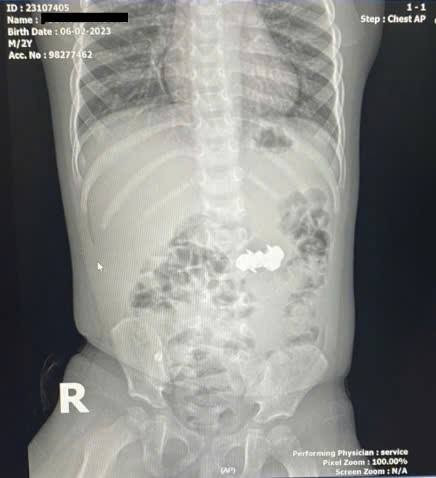

Bé D.H.P. (2 tuổi, trú tại Nghệ An) được gia đình đưa đến viện trong tình trạng nghi ngờ nuốt dị vật trong lúc chơi đồ chơi. Kết quả chụp X-quang bụng cho thấy trong ổ bụng có bốn dị vật kim loại nhỏ hình tròn, có đầu nhọn, nghi là đinh nam châm. Các viên nam châm này đã hút dính nhau trong đường tiêu hóa, tạo nên nguy cơ đặc biệt nghiêm trọng.